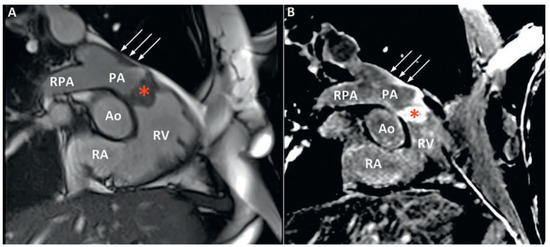

Pulmonary artery sarcomas are uncommon intracardiac tumours with poor prognosis. We report the case of a 69-year-old woman in good health presenting with rapidly progressive dyspnoea and an unfamiliar systolic murmur. Echocardiography revealed pulmonary valve stenosis due to an obstructing mobile mass. Imaging [...] Read more.

Pulmonary artery sarcomas are uncommon intracardiac tumours with poor prognosis. We report the case of a 69-year-old woman in good health presenting with rapidly progressive dyspnoea and an unfamiliar systolic murmur. Echocardiography revealed pulmonary valve stenosis due to an obstructing mobile mass. Imaging studies confirmed the presence of a contrast-enhancing lesion adherent to the valve, extending into the pulmonary trunk and right ventricular outflow tract, and suggestive of malignancy. Endovascular biopsy was attempted with no success. Surgical resection with autologous graft valve replacement and pulmonary artery reconstruction was performed. Postoperative histological examination confirmed the diagnosis of an undifferentiated pleomorphic sarcoma. Pulmonary artery sarcoma should be considered as a rare differential diagnosis in patients presenting with dyspnoea and a crescendo–decrescendo systolic murmur increasing with inspiration. Echocardiography is a useful first diagnostic approach but multi-imaging assessment is almost always necessary for definite diagnosis. Our case provides insights into the challenges met by cardiologists, radiologists and cardiac surgeons in the management of such cases. Full article

Show Figures

Figure 1